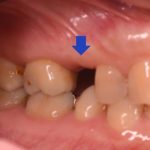

歯が欠けて物が詰まりやすい ダイレクトボンディングによる虫歯治療

治療前 治療後 性別 女性 相談内容 歯が欠けた カウンセリング・診断結果 プラ ...